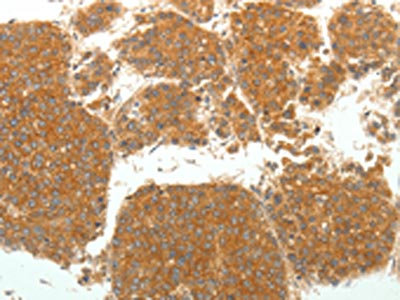

The image on the left is immunohistochemistry of paraffin-embedded Human liver cancer tissue using CSB-PA201090(SIRT4 Antibody) at dilution 1/25. (Original magnification: ×200)

The image on the left is immunohistochemistry of paraffin-embedded Human ovarian cancer tissue using CSB-PA201090(SIRT4 Antibody) at dilution 1/25. (Original magnification: ×200)